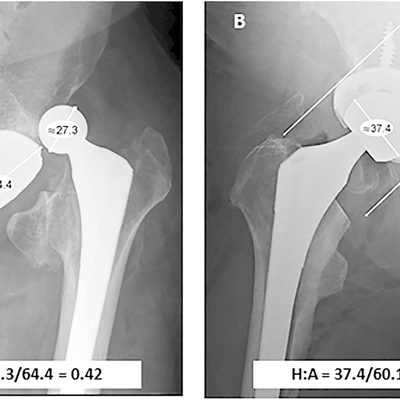

Click on an image below to view more info.